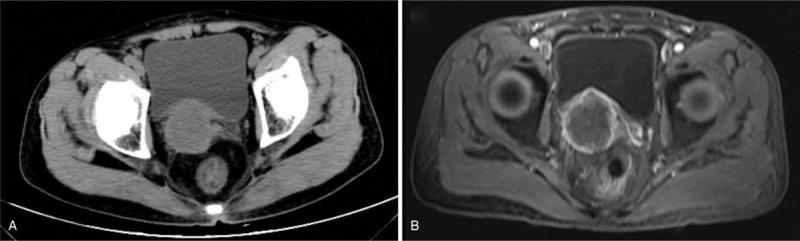

Ultrasonography suggested a hypoechoic mass behind the bladder, meanwhile, computerized tomography (CT) and magnetic resonance imaging (MRI) revealed a 40 mm × 45 mm × 48 mm mixed solid/cystic tumorous lesion in the right seminal vesicle. Postoperative histology confirmed the diagnosis of primary SCC in the seminal vesicle.

超声检查提示膀胱后方有低回声肿块,同时,计算机断层扫描(CT)和磁共振成像(MRI)显示右侧精囊有一个40mm×45mm×48mm的混合实性/囊性肿瘤性病变。术后组织学检查确诊为精囊原发性SCC。